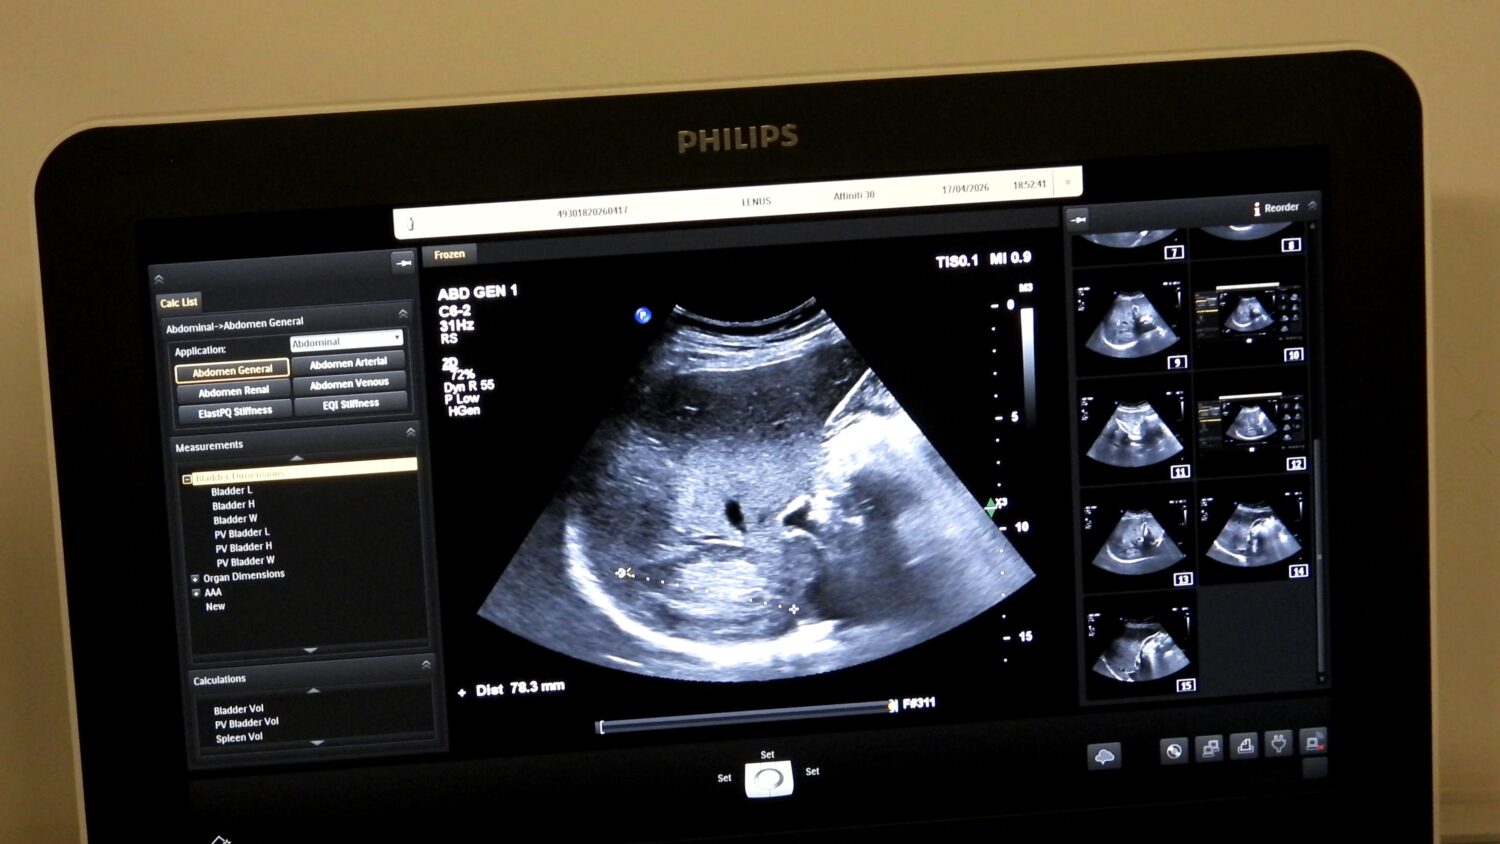

Edukacijom se stvara veći broj educiranih doktora koji mogu samostalno i sigurno raditi ultrazvučne preglede, što direktno povećava dostupnost dijagnostičkih pretraga pacijentima. Što više obučenih ljekara imamo, to su liste čekanja kraće, a građani brže dolaze do pregleda, posebno kada je riječ o preventivnim kontrolama. Organizatori su zahvalili kompaniji Farmavita na podršci realizaciji edukacije, kao i Philipsu, koji je ustupio dodatne uređaje za edukaciju.

Uz Kantonalnu bolnicu Zenica u projektu su učestvovali Ministarstvo zdravstva i Ljekarska komora ZDK, kompanije Farmavita i Philips, te Institut za zdravlje i sigurnost hrane Zenica. Dio vizije kontinuirane edukacije jeste jačanje zdravstvenog sistema u smislu dostupnosti ove dijagnostičke metode pacijentima u njihovim lokalnim zdravstvenim ustanovama. Prema podacima organizatora, certifikate su dobili doktori Alen Mahić, Sabina Bašić, Hana Torlak, Farisa Babić Šabanović, Mirel Čizmić, Dževad Velagić, Dragan Radoš, Selmir Osmanbegović i Belmin Prasko.

Prevencija je ključ dugotrajnog i kvalitetnog života. Redovnim pregledima možete na vrijeme otkriti promjene koje bi mogle utjecati na vaše zdravlje i osigurati pravovremenu reakciju. Ultrazvuk abdomena je jednostavna, bezbolna i sigurna metoda pregleda pomoću koje možemo pregledati organe i strukture koji se nalaze unutar trbušne šupljine. Ovaj pregled igra važnu ulogu u ranom otkrivanju promjena koje mogu dovesti do narušavanja zdravlja i razvoja bolesti.

Ultrazvuk abdomena je posebno važan za ljude koji imaju faktore rizika, poput porodične istorije bolesti abdomena, dijabetesa, visokog krvnog pritiska ili gojaznosti. Redovni pregledi omogućavaju praćenje stanja organa i sprječavanje komplikacija. Pregled se izvodi u ležećem položaju – ljekar pregleda abdomen uz pomoć sonde na koju se nanosi ultrazvučni gel. Pregled traje od 15 do 30 minuta, bezbolan je, uređaj nema zračenja i potpuno je siguran za pacijente.